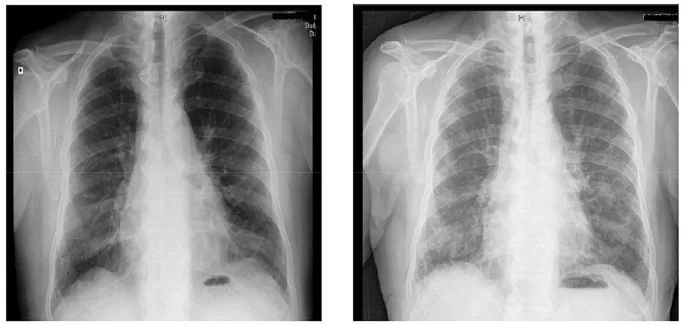

X 线也常用来看肺,正常肺里都是气体,密度低,在片子上是黑色的,有高密度的结节、钙化点会非常明显。

呼吸科还有个说法叫「白肺」,是指拍出来的片上肺变成大片白色,通常意味着情况危急,说明肺里面的炎症、渗出或者纤维化已经非常严重了。

图片来源:link.springer.com